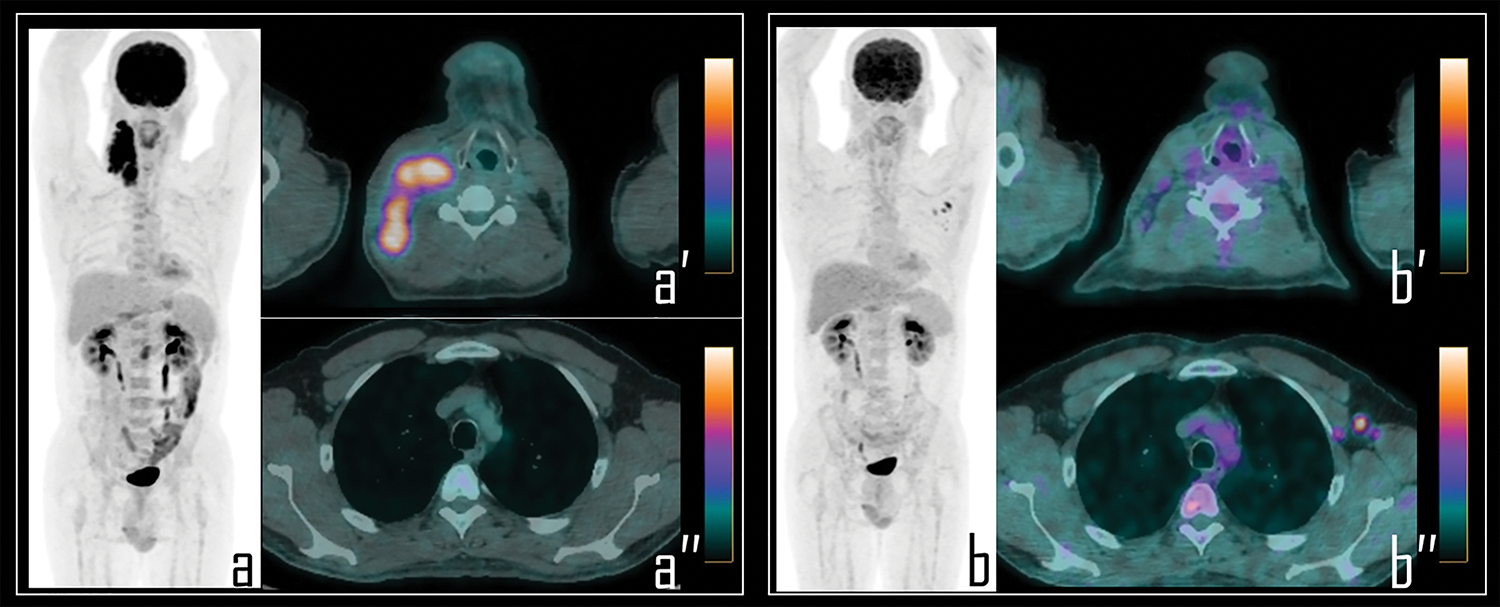

Among 104 patients with vaccine-related 2-[18F]FDG false positive axillary findings, 36 patients (34%) received intravenous chemotherapy administration for lymph nodes metastases from somatic cancers or lymphomas, in the 15 days preceding the PET/CT scans (n.8 lymphomas, n.7 colon cancer, n.1 mesothelioma, n.12 ovarian cancers, n.8 lung carcinoma). In this subgroup of patients, 30 subjects presented complete response to therapy (Fig. 4) and 4 patients showed persistent disease; in 2/36 patients, lymph nodal progression disease was documented with newly diagnosed, infra-diaphragmatic, lymph node metastases.

Figure 4: A 25-year-old male patient underwent 2-[18F]FDG PET/CT during the staging of Hodgkin’s lymphoma. PET (a) demonstrated pathologic tracer uptake in right lateral cervical lymphadenopathies. Axial PET/CT view well displays pathologic lymphadenopathies in the neck (a′) while no foci of uptake were detected in the axillary regions (a″). Subsequently, patient was submitted to chemotherapy and, 9 days before the interim PET/CT, to COVID-19 vaccine administration in the left arm.

Note: Interim PET/CT (b) showed response to therapy with reduction of the uptake in the neck, more evident in axial PET/CT view (b″); conversely, three lymph nodes with moderate 2-[18F]FDG uptake were detected in the left axilla, as displayed in axial PET/CT view (b″), presenting SUVmax 2.8. These findings were linked to the previous vaccine administration.

A single case of COVID-19 related tracer uptake in axillary lymph node was also documented during a whole body [18F]Choline PET/CT, among 31 prostate cancer patients examined with this tracer. Registered SUVmax in this lymph node was 2.3 (Fig. 5).

Figure 5: A 65-year-old prostate cancer patient underwent [18F]Choline PET/CT due to biochemical relapse of disease, two years after radical prostatectomy. PSA at the time of the scan was 0.4 ng/mL. Patient also underwent COVID-19 vaccine injection in the left arm 6 days before the exam.

Note: PET imaging (a) was negative for disease relapse but showed a single area of focal [18F]Choline uptake in the left axilla, corresponding to a 1 cm wide, ovoid lymph node, displayed in axial PET/CT view (b), with fatty hilum detectable in the axial, co-registered low dose CT (c). This lymph node was considered as reactive, following vaccine administration; SUVmax was 2.3.